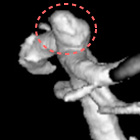

脳動脈瘤塞栓術

脳動脈瘤が破裂して出血するのを防ぐために、脳動脈瘤にコイルを詰めて血液が入り込まないようにする手術です。

術後に血管撮影を行うと、コイルで置き換わった脳動脈瘤は造影剤が入らないため描出されなくなります。